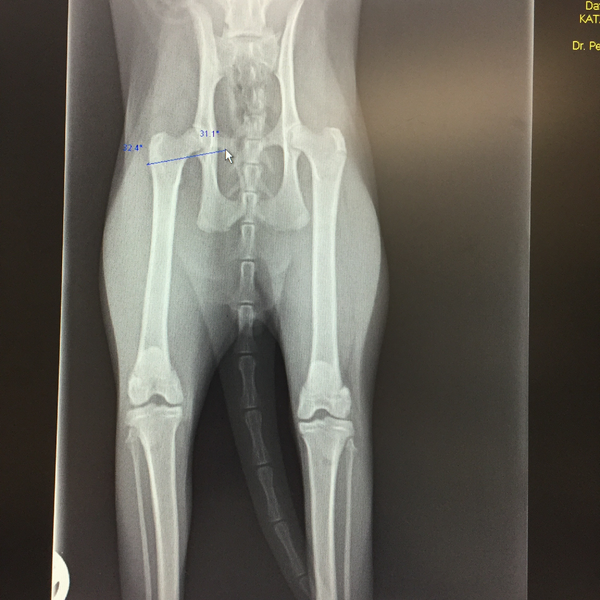

Die Röntgenuntersuchung ist nach wie vor ein unverzichtbares diagnostisches Verfahren, das essenzielle Einblicke in Herz-, Lungen-, Verdauungs- und Harnwegserkrankungen bietet. Besonders bei der Untersuchung des Skelettsystems – ob es sich um Frakturen, degenerative Veränderungen, Wachstumsstörungen oder angeborene Fehlbildungen handelt – ist das Röntgen nach wie vor das Mittel der Wahl.